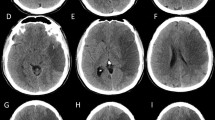

Computed tomography predictors identified include hypodensity >50 % of MCA territory on initial computed tomography [24, 25, 31], pineal displacement >4 mm within 48 h of onset [32], internal carotid artery T occlusion [28, 33], combined ICA and MCA occlusion [34], involvement of vascular territory other than MCA (eg, ACA, PCA, anterior choroidal) [25, 23], hyperdense MCA sign [31, 35], attenuated corticomedullary contrast within 18 h of onset [35], and perfusion deficit in >66 % of MCA territory at 6 h after onset [36]. MRI predictors include apparent diffusion coefficient (<80 %) [28] or diffusion weighted imaging [34] volume lesion volume >82 mL within 6 h of onset, and time-to-peak on MRI perfusion maps >162 mL [28].